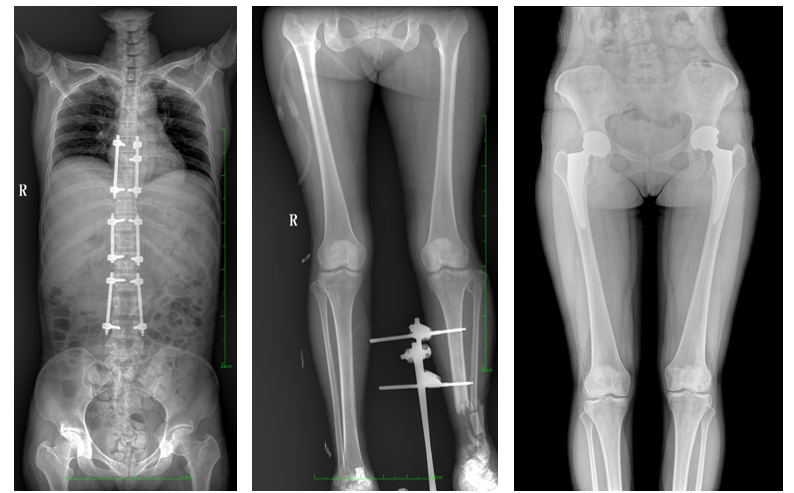

普愛醫療自主研發的一款數字化X光機——PLX8600大視野平板動態DR,擁有43cm*86cm超大有效視野,可一次性拍攝全脊柱、雙下肢的影像視野。使全脊柱及雙下肢能夠得到完整清晰的成像,為臨床在脊柱側彎畸形和下肢骨關節病變診斷、治療方案制定及治療后復查提供精準的測量。